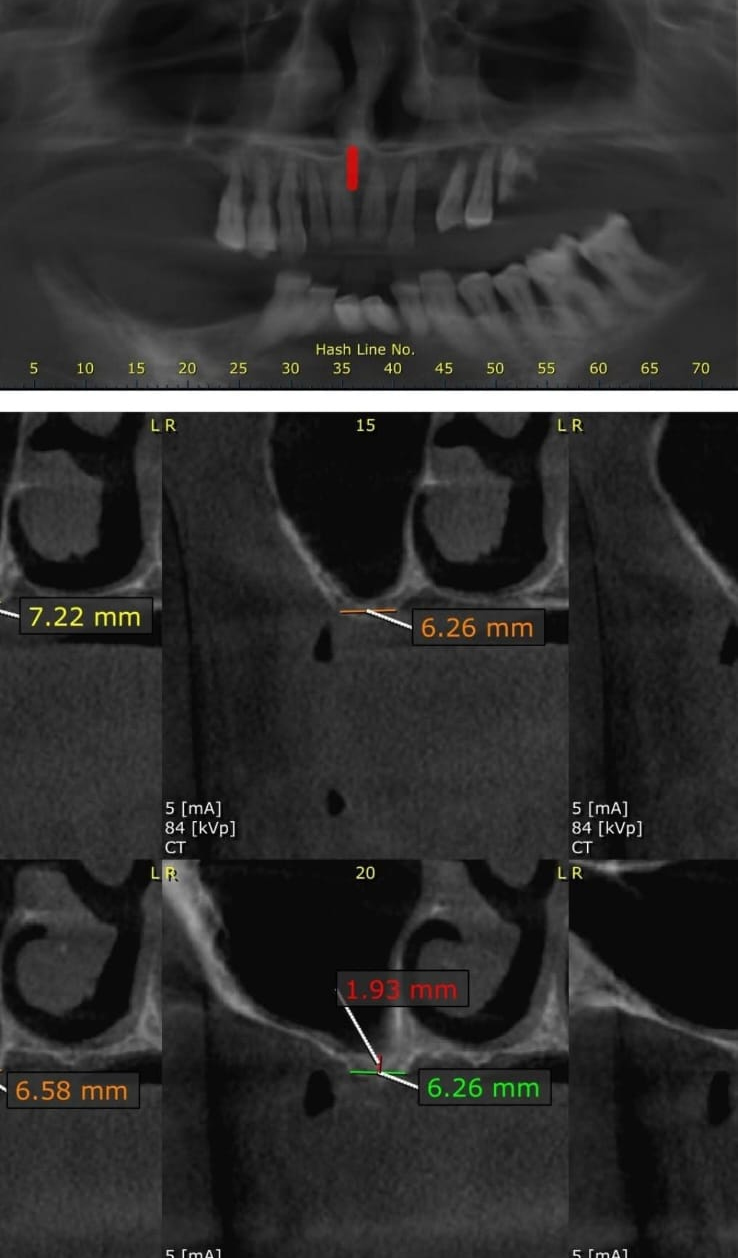

Full Mouth Implant Case

Anterior Implants

Full Mouth Implants with all Ceramic Crowns